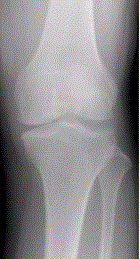

问题 患者女,54岁,右膝关节痛。实验室检查:类风湿因子阳性,除外膝关节类风湿性关节炎。X线检查结果如下图。 类风湿性关节炎早期的病理改变是

选项 A.关节软骨变性 B.关节滑膜增生 C.滑膜血管翼形成 D.关节强直 E.关节边缘骨侵蚀

答案 B